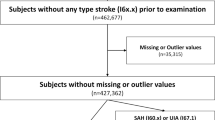

Patient enrollment

A total of 10,000 MRI and MRA images from participants who underwent Brain Dock examinations between December 2018 and July 2019 using the remote imaging system were analyzed, excluding cases with poor image quality or those who stopped the examination because of feeling sick during the process (Fig. 1). In addition, no cases of post-craniotomy or having clips or other surgical instruments in the cranium were included. The age; sex; BMI; medical history, including hypertension, diabetes, dyslipidemia, arrhythmia, dementia, and stroke; surgical history; and the presence or absence of UCAs of all participants were recorded. The presence or absence of a UCA was classified into the following three categories: “definitive,” “none,” and “suspicion.” A “suspicion” case was defined as a case that, in the judgment of the reading physician, could not be completely ruled out as a definitive UCA and was therefore used as a positive case (i.e., presence of UCA) in the analysis. Ground truth determination involved an initial diagnosis by the radiologist, followed by a final diagnosis by the neurosurgeon who reviewed the diagnosis of the radiologist. Both initial and final diagnoses were recorded in the report system. Optionally, both the radiologist and neurosurgeon were allowed to provide detailed feedback about the AI output, labeling each candidate output as either true positive or FP and recording missed UCA (false negative). This information was recorded in the AI feedback database (Fig. 2).

The diagnosis algorithm was tuned on April 7, 2019. The MRI and MRA images of exactly 5000 consecutive participants acquired before and after the tuning of the algorithm were both extracted. The abovementioned examination parameters, along with the results of the final diagnosis of UCA recorded in the report system, were compared and analyzed as the primary analysis. Sensitivity and FPs/case metrics were computed for all 10,000 cases.

Subsequently, a secondary analysis was performed only on the cases for which detailed AI feedback was provided. We extracted 1359 cases where the feedback was given before algorithm tuning and 859 cases where the feedback was given after tuning. The examination parameters and rating of each AI candidate output were again compared and analyzed. The assessment of diagnostic accuracy for UCA diagnosis was specifically based on the comparison of sensitivity and the FP/case.